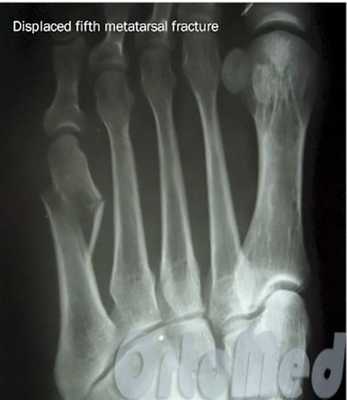

Если перелом сопровождается значительным смещением костных отломков (более чем на половину ширины плюсневой кости) решается вопрос об операции.

Операция при переломе плюсневой кости

Показанием к операции при переломе является смещение отломков плюсневой кости больше чем на половину ширины кости.